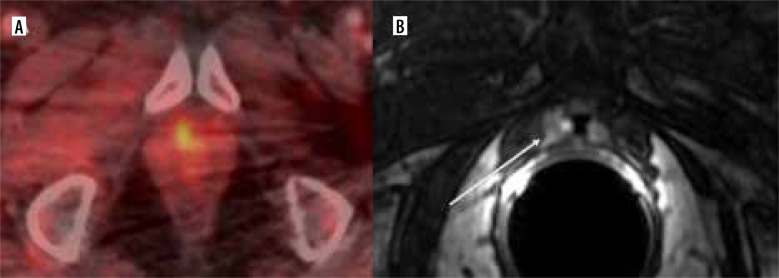

Abstract Image